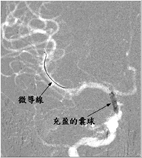

此時右半邊大腦處於嚴重缺血的狀態,若無法即時將血管打通,將會有大範圍中風的情況產生,過去的文獻報導這類的患者死亡率可以高達51%,在集合本院小兒神經科專家與腦中風中心神經放射線科專家共同會診評估後,建議積極使用血管內介入性治療,打通腦部阻塞的血管。醫療團隊將一條微細的導管穿過狹窄的內頸動脈,深入患者右側中大腦動脈,在6小時的黃金時間內,成功將中大腦動脈的血栓溶解,並將原先內頸動脈剝離而狹窄的血管,利用囊球擴張與支架置放,重建血管使其恢復原有的管徑大小,患者出院時除了手部細微動作受到影響外,看不出身體活動有中風過的症狀,目前追蹤已將近一年,無中風再發的情形。

動脈內血栓溶解圖,左邊圖是血栓溶解前,右邊圖是血栓溶解後